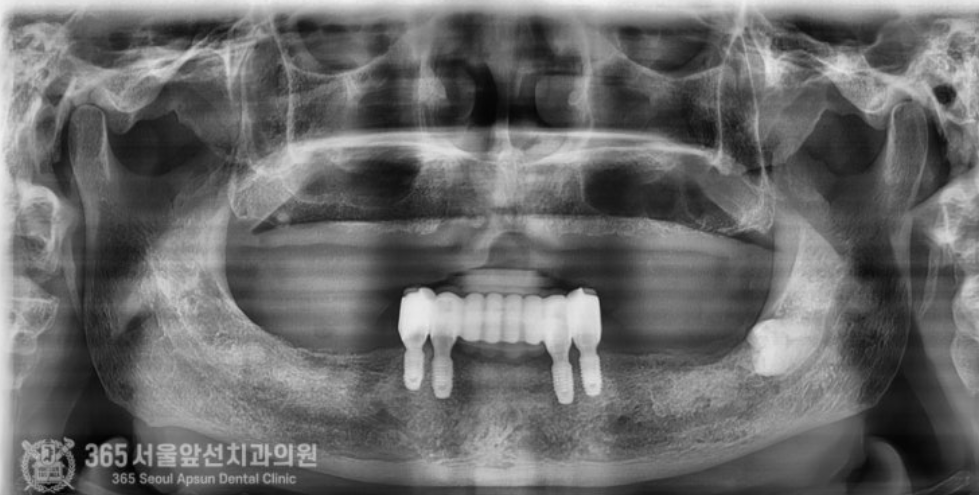

촬영일시 : 2024.05.01 처음 내원 당시 엑스레이 사진입니다. 보시다시피 거의 치아가 남아있지 않고 그나마 남아있는 치아들도 상태가 매우 좋지 않습니다. 아래턱에 치아가 몇개 남아있으나 흔들리고 썩어있는 상태여서 어쩔 수 없이 발치를 하기로 결정하였습니다 ㅠㅠ 이렇게 치아가 있긴 있으나 상태가 좋지 않은 경우에는 오히려 안좋은 치아를 남겨놓고 치료계획을 세울 경우 추후 문제가 되어 전체적인 치료과정에서 문제가 되는 경우가 많기에 발치를 해야할 치아는 늦지 않게 발치를 하고 보철치료나 임플란트 치료로 대체해주는 것이 중요하겠습니다. 환자분께서는 비용 상의 문제로 인해 전체 임플란트를 너무 부담이 되신다고 하셔서 임플란트는 최소한의 갯수로 식립하고 식립된 임플란트를 이용하여 틀니를 튼튼하게 사용할 수 있도록 임플란트 틀니 치료를 하기로 결정하셨습니다.

촬영일시 : 2024.05.14 임플란트가 잘 식립된 사진입니다. 추후 아래 틀니를 붙잡아줄 중요한 녀석들이죠 ㅎㅎ 이렇게 심어놓고 뼈와 임플란트가 붙을때까지 시간을 기다려줍니다.

촬영일시 : 2024.08.09 완성된 임플란트 브릿지 엑스레이 사진입니다. 짱짱하게 생겼습니다 ㅎㅎ 이제 브릿지를 이용해서 위아래 틀니를 제작해줍니다. 이때 턱의 높이를 결정하고 턱의 위치를 잡아주는 과정을 거쳐 정확한 위치에 보철물을 제작하게 됩니다.